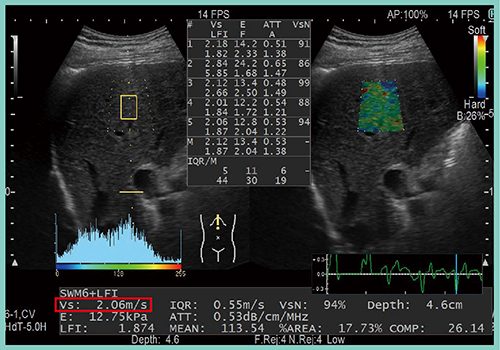

前述の症例の肝臓を測定すると,Vs値は2.06m/sであった(図1)。このVs値の臨床的有用性を検証するために,当院と,近畿大学および愛媛大学が共同研究を行った。

図1 症例:Combi-Elastoでの測定結果